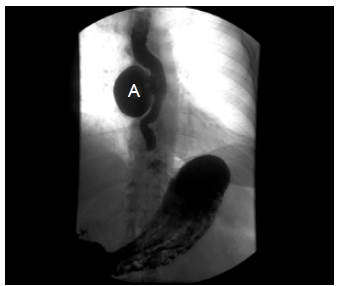

Mujer de 72 años de edad, con cuadro clínico de un año de disfagia y atragantamiento con alimentos sólidos, que había requerido tratamiento endoscópico. Se realiza endoscopia de vías digestivas altas que documenta un divertículo esofágico en tercio medio, y manometría esofágica de alta resolución, sin trastorno motor. El esofagograma (figura 1) y la tomografía computarizada de tórax (figura 2) muestran un divertículo en tercio medio de esófago, lateral derecho, de 7 cm de diámetro y base de 2.5 cm de diámetro. De manera programada se lleva a cabo diverticulectomía esofágica por toracoscopia, en decúbito prono (figura 3), sin complicaciones.

Figura 1 Divertículo esofágico de tercio medio, lateral derecho (A).